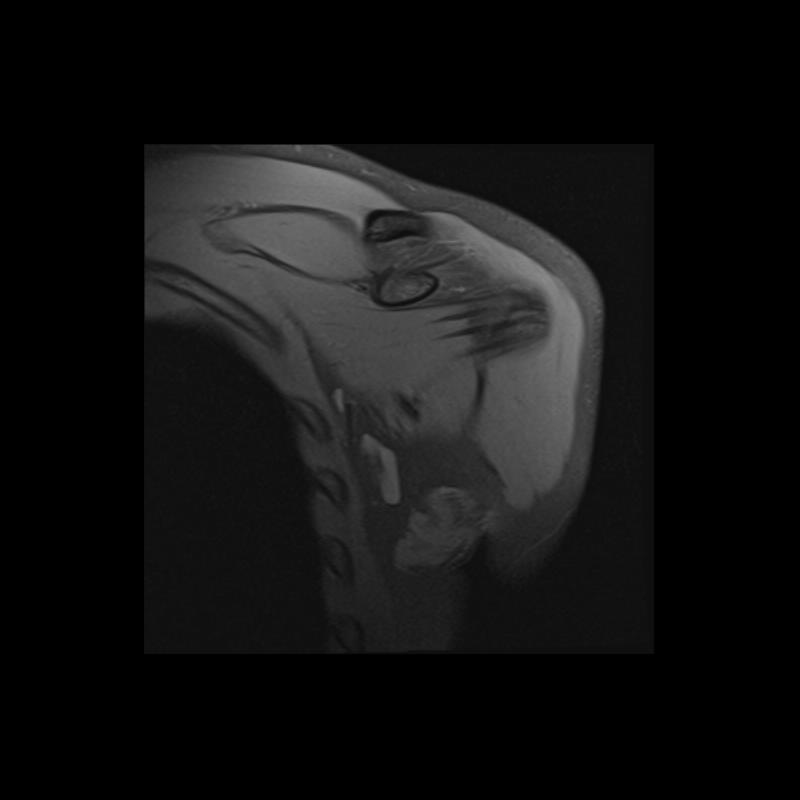

Shoulder MRI Anatomy